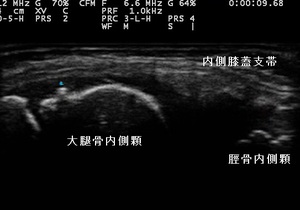

川越市小学生 膝の痛み 膝の打撲

右膝蓋内側 超音波長軸像 左膝 同部健(正常)側

川越市小学5年生、男児。 膝内側の痛み、膝の打撲。

【原因】

教室で友達と遊んでいた際、滑って右膝の内側を床に強打してしまいました。1日経過しても痛みが引かずに

むしろ痛みがひどくなってしまいました。

受傷翌日に当接骨院へ来院されました。右膝蓋内側の圧痛と熱感が認められましたが、腫れはありませんでした。

超音波観察を行ったところ、右膝蓋大腿関節面より内側に滑膜や脂肪組織に挫滅、その周囲に内出血や浮腫

がある様子が認められました。(左上画像の丸の囲み)